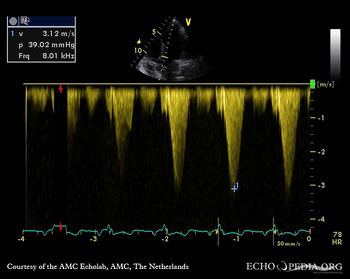

Continuous-wave doppler signal: dynamic gradient in LVOT Pulsed-wave doppler signal of transmitral flow

Continuous-wave doppler signal: dynamic gradient in the middle of left ventricle